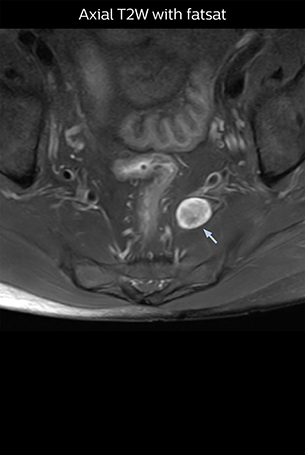

“NerveVIEW is really useful for those cases where a nerve disorder is strongly suspected based on the clinical examination but our regular MRI images do not show any findings. These atypical herniations and spinal canal stenosis, occurring in 5% to 15% of the total lumbar herniation/stenosis cases are our main target when using NerveVIEW,” says Dr. Yabuki.

“The intra-luminal signal of veins, especially around the intervertebral space, can be suppressed well with NerveVIEW. As a result, we can easily observe the detailed nerve structure around the posterior ganglion,” he says. “This is why we use 3D NerveVIEW for intraforaminal stenosis and extraforaminal stenosis/herniation (lateral disc herniation). On the other hand, if herniation is suspected to exist inside the dorsal root ganglion (DRG), balanced TFE or ProSet-FFE is applied. NerveVIEW is not suitable for evaluating the median type of herniation.” The SE-EPI DWI-based method for MR neurography works well for large FOV exams like whole-body MRI, but focal examination of nerves is often limited by the attainable spatial resolution (both inplane and slice direction) and geometric distortion. “3D NerveVIEW achieves higher in-plane resolution – close to our other routine spine sequences – and the source images can be used instead of adding a fat-suppressed T2-weighted sequence,” Tanji says.